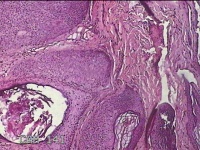

右侧肩部红色结节

性别

女

年龄

48岁

临床诊断

皮下结节

一般病史

发现右侧肩部结节3年余。

标本名称

大体所见

灰白暗红色结节0.5x0.3x0.2cm一个,表面糜烂。

基底细胞乳头状瘤